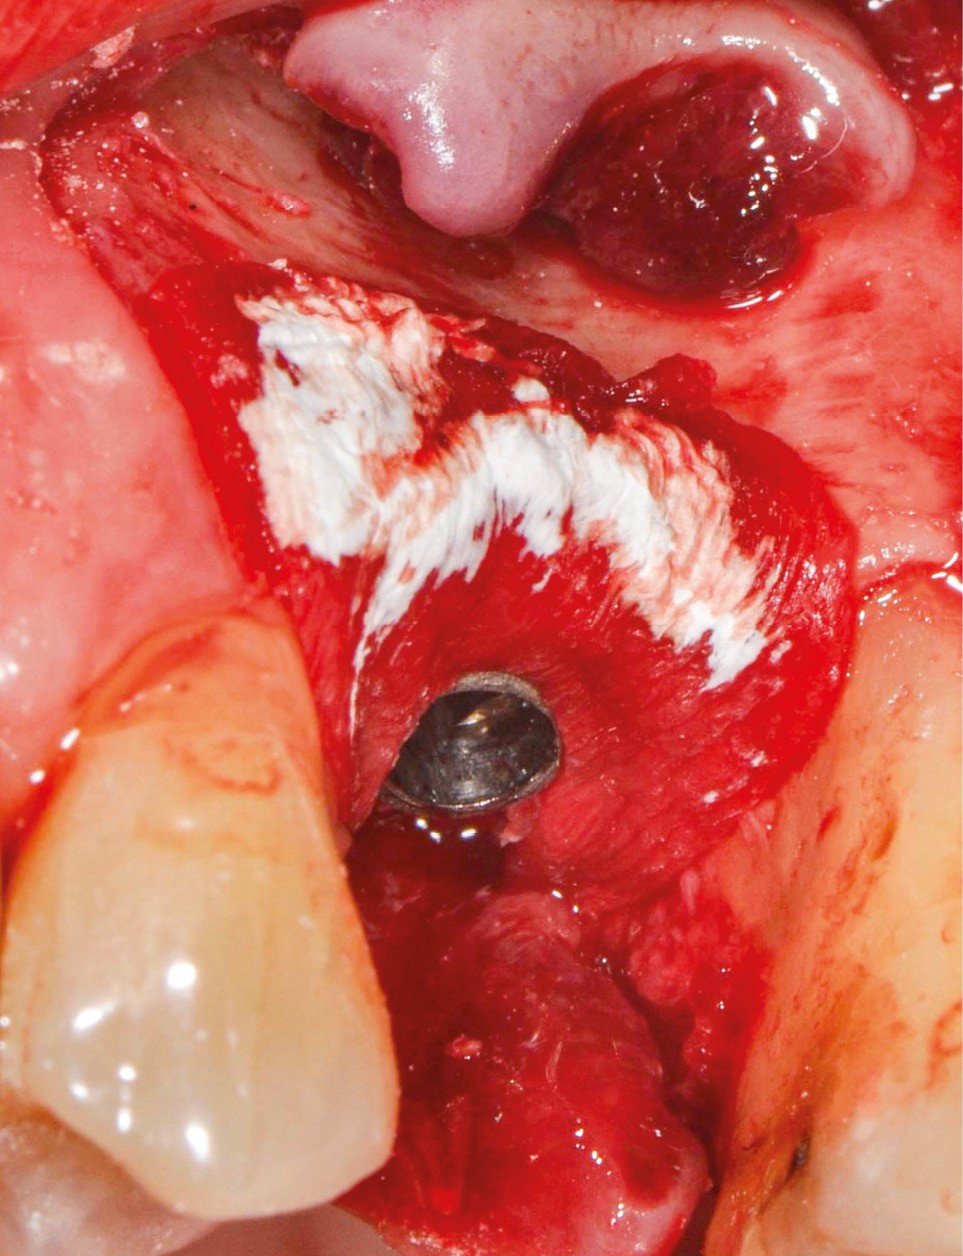

Chez cette patiente, le traitement de la péri-implantite a été réalisé à l’aide d’une technique de régénération osseuse guidée péri-implantaire, dont l’indication a été principalement motivée par la morphologie du défaut osseux. Au-delà de la maîtrise du geste chirurgical, le bon résultat obtenu à trois ans est intimement lié à sa coopération en termes de suivi et de contrôle de plaque.